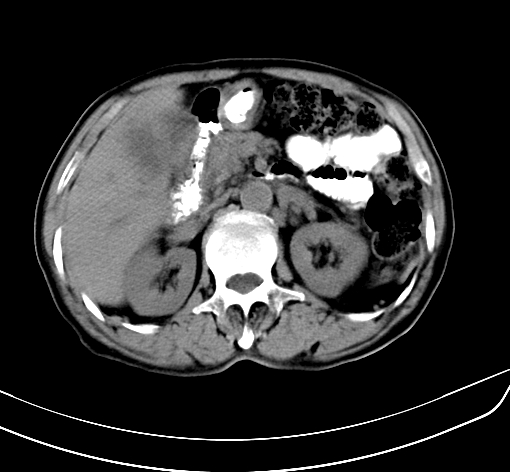

病人 男 70 咳嗽 胃部不适 2月余

胆囊壁增厚,与临近肝实质边界不清,临近肝实质内可见大片边界不清之低密度区,肝门区密度亦有减低,部分结构不清,尾叶前方可见块状影,肝右叶可见多枚边界不清之圆形低密度区,肝内胆管扩张征象,结合病史考虑1胆囊癌肝内转移,肝门区淋巴结转移,门脉癌栓待排2肝内胆管扩张3建议增强扫描

肝脏多发大小不等低密度灶,边界不清,肝门区结构不清,肝内胆管轻度扩张,胆囊密度不均匀,内见软组织样密度影,与相临肝脏边界不清.考虑:1、胆囊ca侵犯肝脏并肝内多发转移,肺上也有结节影,转移?建议强化扫描.2、胃充盈不好,如怀疑有病变最好建议做相关检查.

胆囊壁增厚,周围模糊不清,肝内多发低密度影,胃充盈欠佳,胃壁增厚,外形尚规整,考虑胆囊炎、胆囊癌肝内转移?建议胃肠道进一步检查或增强扫描。